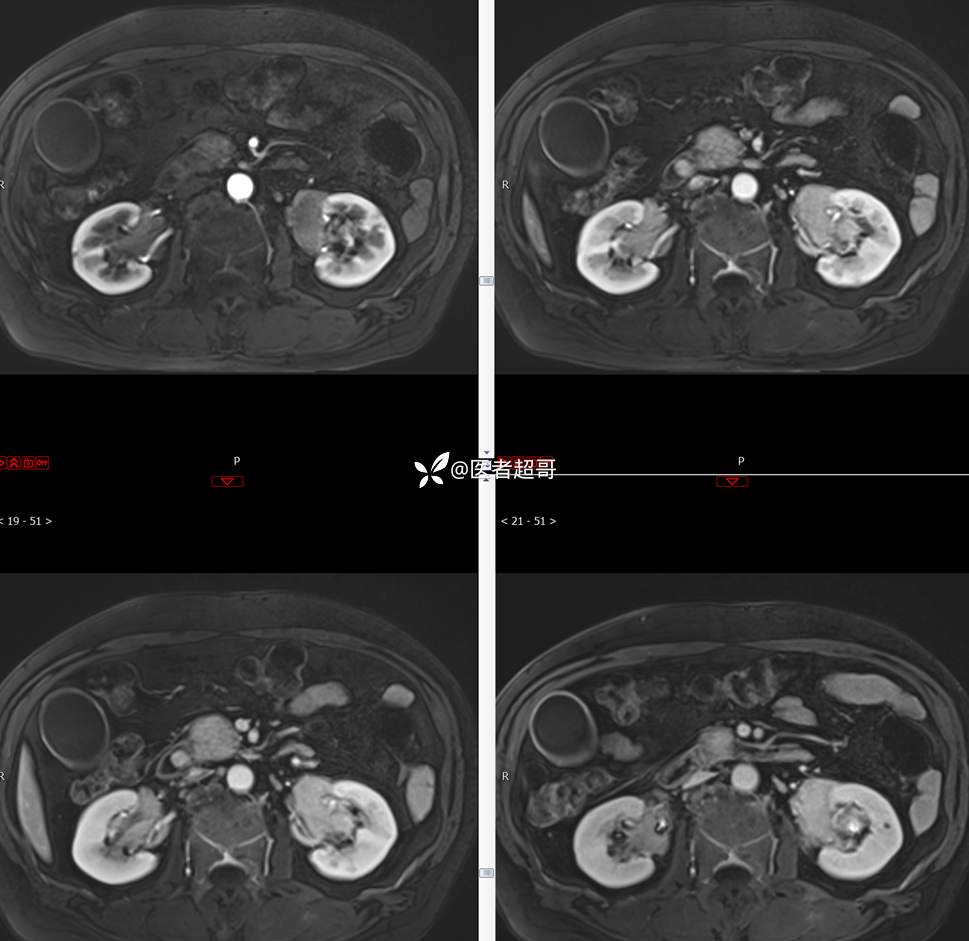

【影诊笔记772】腹痛就诊,发现肾脏病变,CT、MRI齐全,请高诊!

男,63岁 0200825 01

主 诉:间断腹痛15天

现病史:患者15天前无明显原因及诱因出现腹部疼痛不适,呈间断性钝痛,右下腹为著,无尿频、尿急、尿不尽,无发热、寒战,无腹胀。于市中心卫生院住院治疗,超声示:胰头低回声包块,胆系扩张,左肾囊肿,胆囊壁毛糙,胆囊内胆汁淤积。患者为求进一步诊治,遂以“肾盂肿瘤”收入院,患者自发病以来,神志清,精神可,饮食睡眠可,大便无明显异常,近期体重无明显增减。

既往史:既往体健